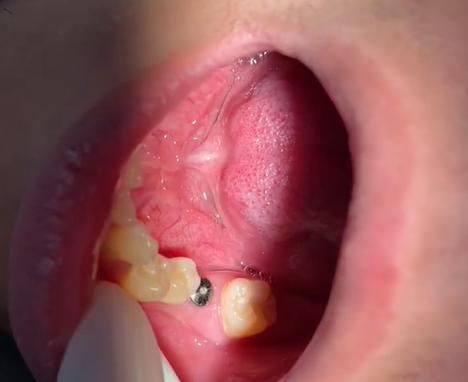

- 切口: 医生会在覆盖种植体的牙龈上做一个小切口(通常是环形或弧形切口),像“翻开盖子”一样暴露下方的种植体顶部。

- 暴露种植体: 小心地分离牙龈组织,完全暴露种植体的连接平台。

- 连接基台: 选择合适高度的基台,将其旋入或按压到种植体的接口上,确保连接紧密。

- 牙龈成形与缝合:

- 医生会修剪牙龈组织,使其形成理想的轮廓。

- 将牙龈组织精细地缝合在基台周围,形成袖口,有时会使用愈合基台,这是一个高度略高于最终基台的临时基台,目的是引导牙龈更好地塑形,为后续安装永久基台和牙冠创造更好的条件,二期手术时安装的基台也可能是最终基台,取决于医生的设计和方案。